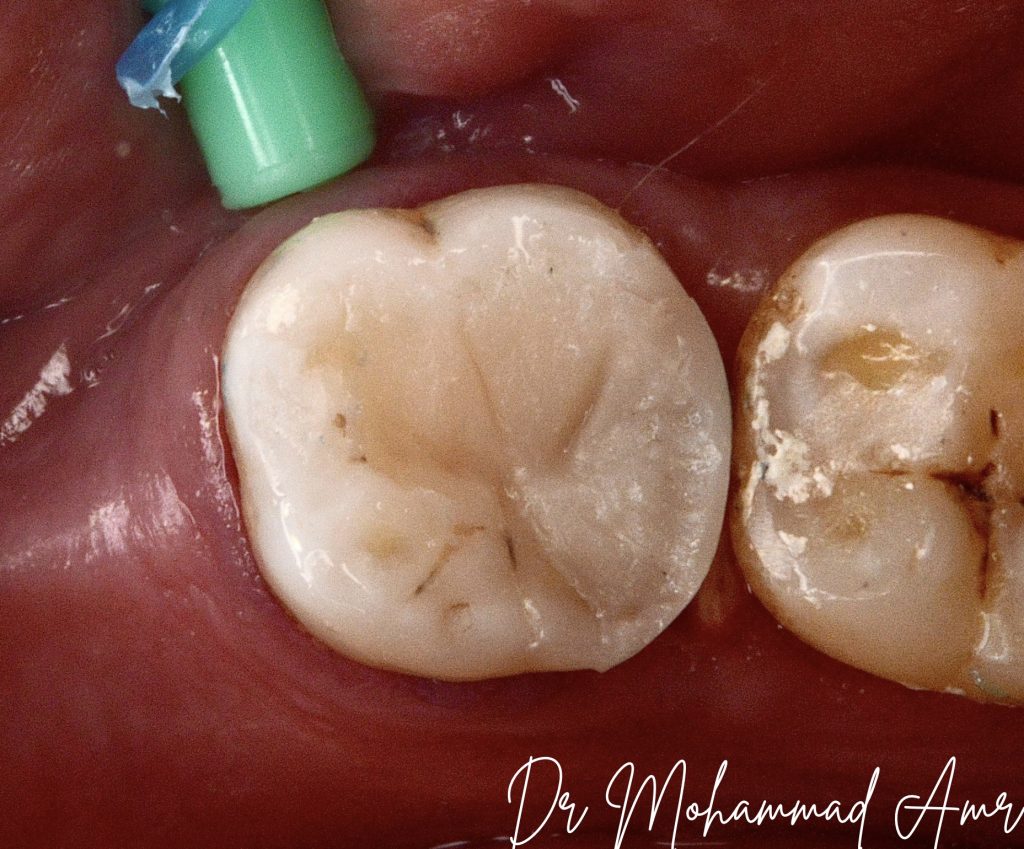

Challenging access cavity at first:

- Buccally shifted (note the trial for finding DL orifice but was in the wrong place .. the right place located later, Alhamdullah).

- Distal canals were too close to distal margin, clear now after complete cleaning & shaping,

Alhamdullah.